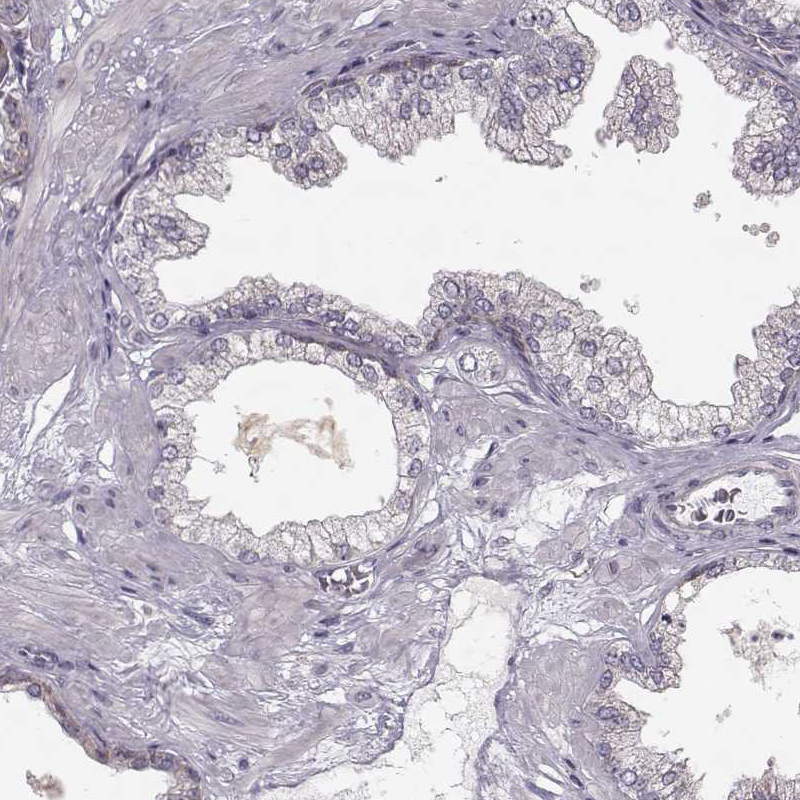

Immunohistochemistry analysis in human testis and prostate tissues using HPA040025 antibody. Corresponding HMMR RNA-seq data are presented for the same tissues.